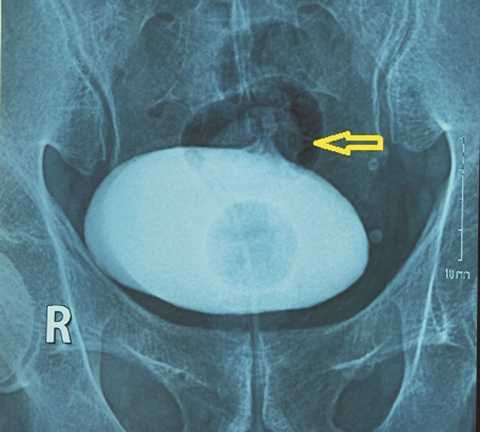

Bị mô viêm mãn tính, rò bàng quang - đại tràng chậu hông, bệnh nhân nhập viên với lý do đi tiểu ra cọng hành, ăn rau tiểu ra rau, tiểu ra phân.